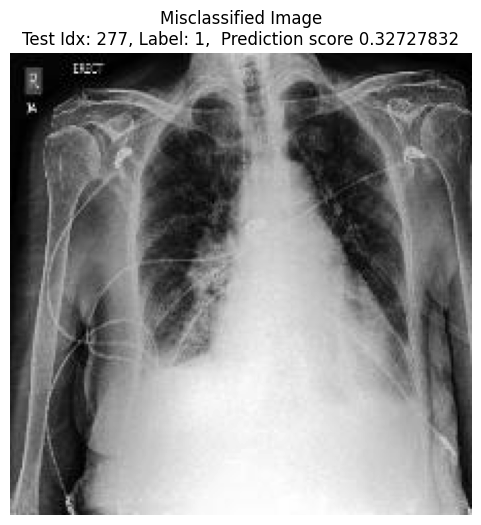

We also visualize the top 10 most harmful and helpful training samples for a given misclassified test sample. Examples for MNIST and CheXpert are shown in Fig. 4 and 5, respectively.

CheXpert

As shown in Fig. 5, only three out of the ten most harmful training points come from the flipped label distribution. However, considering that only 20% of training samples are flipped, the fact that flipped samples appear among the most harmful more frequently than random chance would suggest is still significant. In addition, the harmful training samples include some scans with unusual characteristics, such as odd patterns or artifacts.